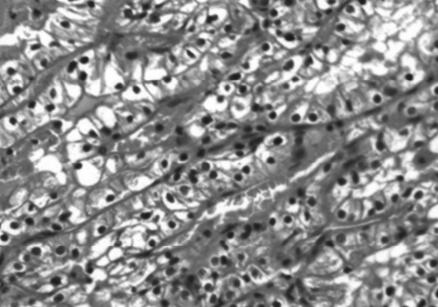

图2,病理诊断:右肾透明细胞癌FurhmanⅡ级